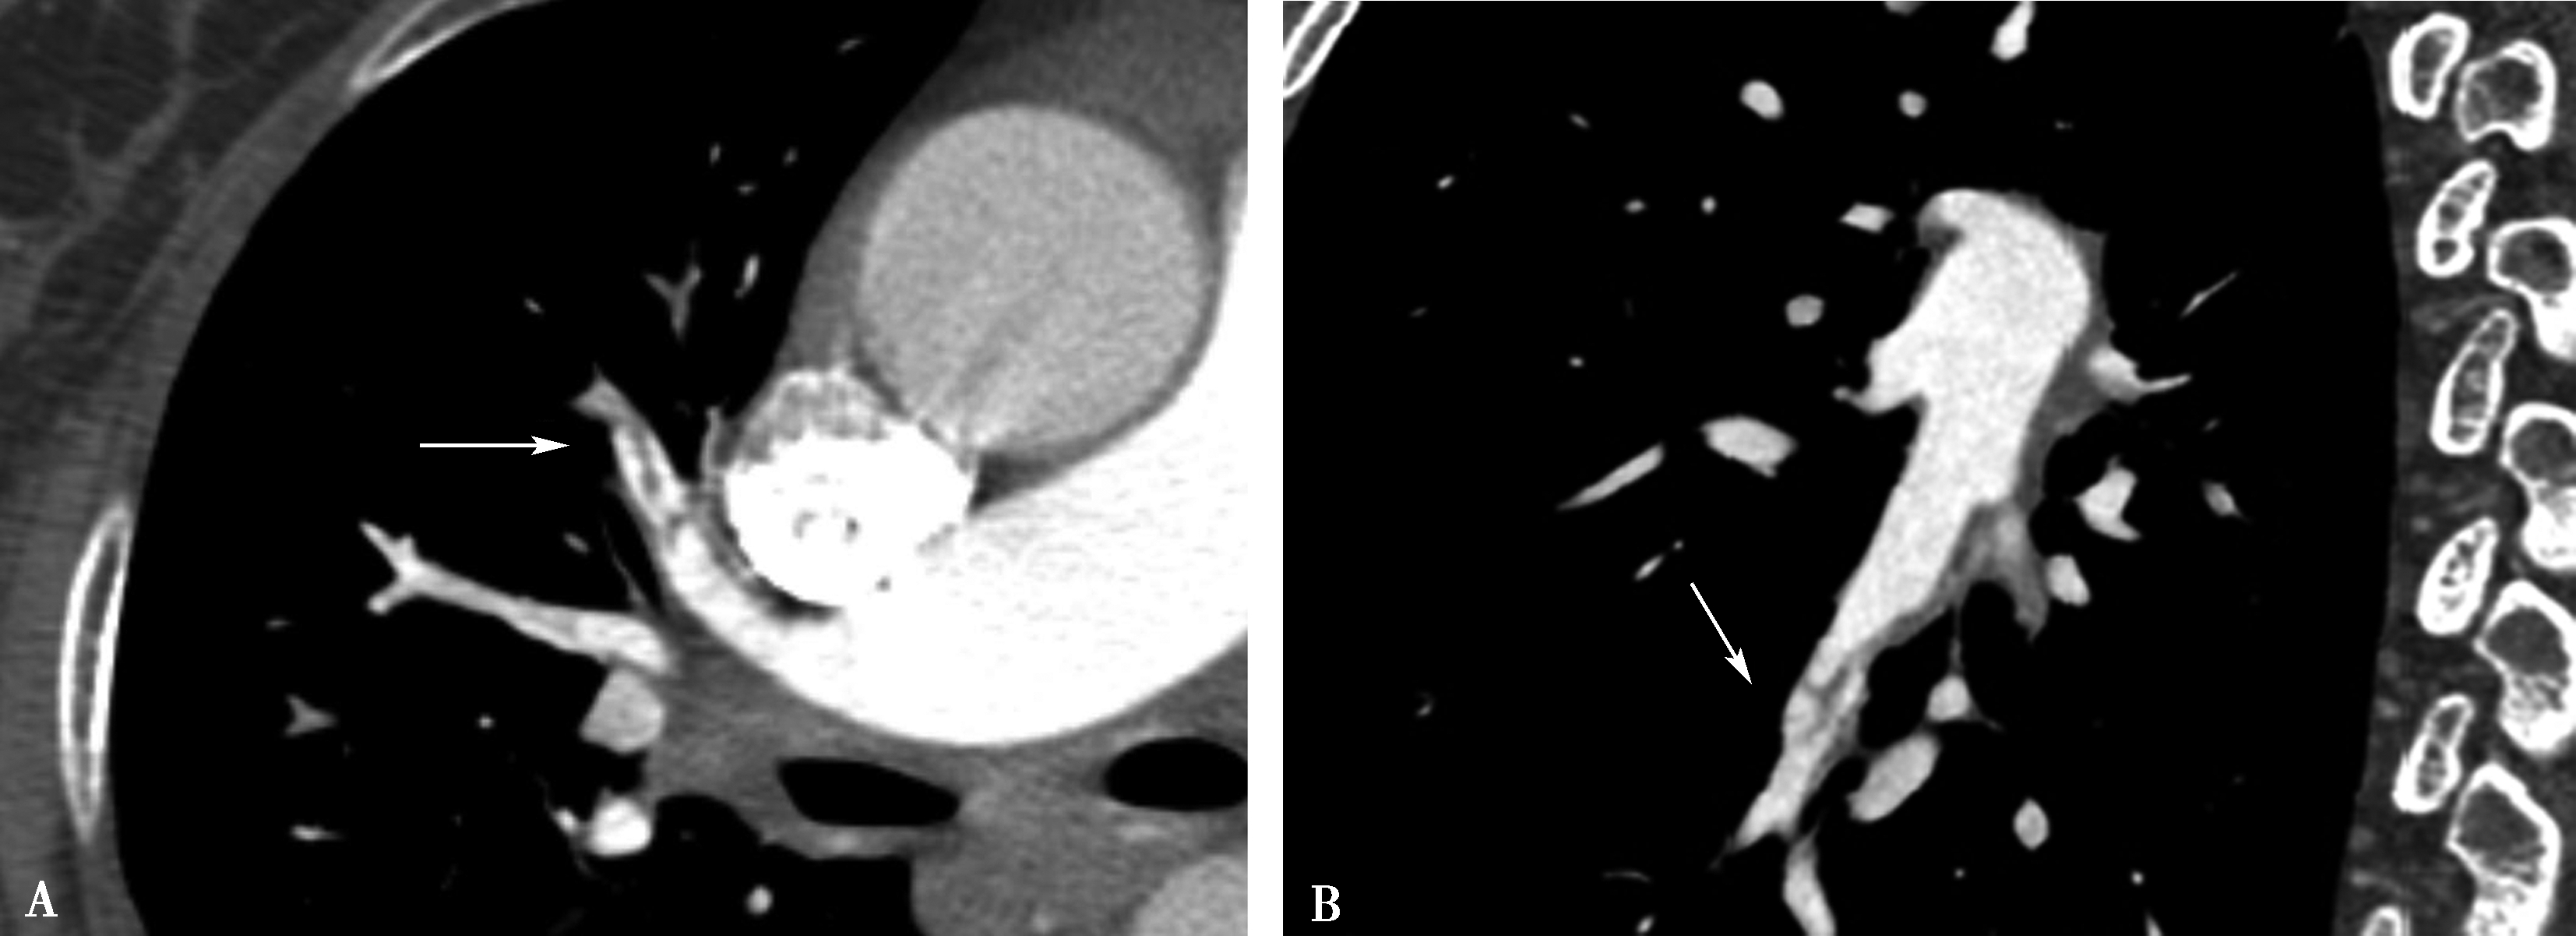

5.扫描采用对比剂智能自动跟踪触发技术,监测层面设定在气管分叉平面,ROI定位于肺动脉干,触发阈值定义为100Hu(图8-1-3,图8-1-4)。

图8-1-3 对比剂智能自动跟踪触发技术

造影剂智能自动跟踪触发技术能够准确获得扫描启动时间点并及时启动扫描

图8-1-4 常规肺动脉CT造影横断图及重建图像